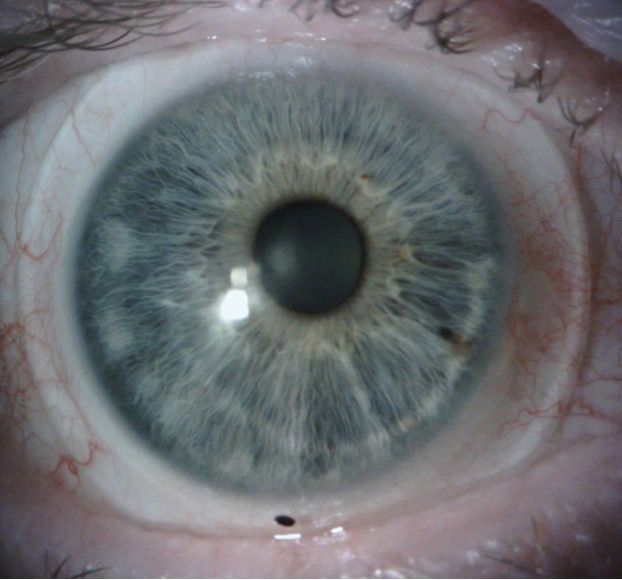

The patient achieved clear, single vision and a rotationally stable and acceptable fit with the final dispensed scleral lenses. The final lens parameters for the OD lens were a diameter of 16.8 mm, a base curve of 8.04 mm, a sag of 5.157 mm, with a power of -5.25 D. Center thickness was 0.38 mm, the flat scleral landing zone was 3.00, and the steep landing zone was -6.00 with 2 pd BD. For the left eye, the diameter meas-ured 16.8 mm, the base curve was 8.04 mm, with a sag of 5.158 mm, with a power of -5.50D, a center thickness of 0.37 mm, a flat scleral landing zone of 3.00, and a steep landing zone of -6.00, with 2 pd BU. The final lens material for both lenses was tisilfocon A OU. Final scleral lens acuities were 20/20 OD, OS, OU with single and binocular vision.

Figure 3: Dispensed scleral lenses showing satisfactory centration and edge alignment with no blanching of conjunctival circulation. Left: OD; right: OS.